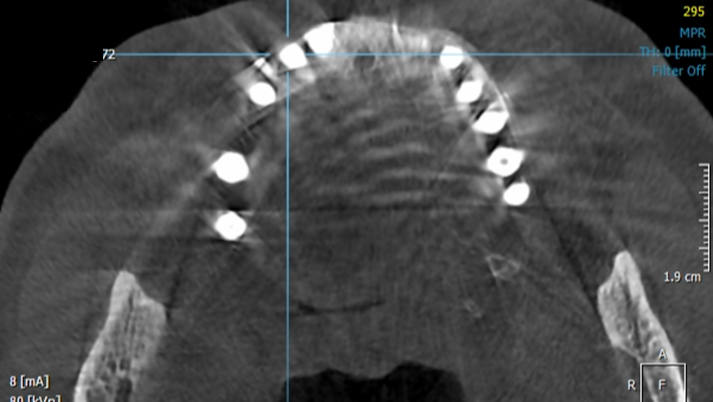

Clinical case: Peri-implantitis treatment case using titanium or NiTi brush

- Courtesy of Dr. Dae-Hee Lee, South Korea -

Dr. Dae-Hee Lee,Maxillary Anterior,Peri-implantitis,Bone regeneration,Aesthetic zone,#21,#22,GBR,Titanium Brush Set